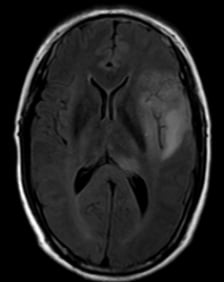

患者为一名50岁男性,因阵发性头晕头痛就诊。2021年7月,颅脑MRI检查提示左侧额颞叶及丘脑存在占位性病变,高度怀疑为胶质瘤。

图1. 初诊时颅脑MRI检查结果(2021.7.24)